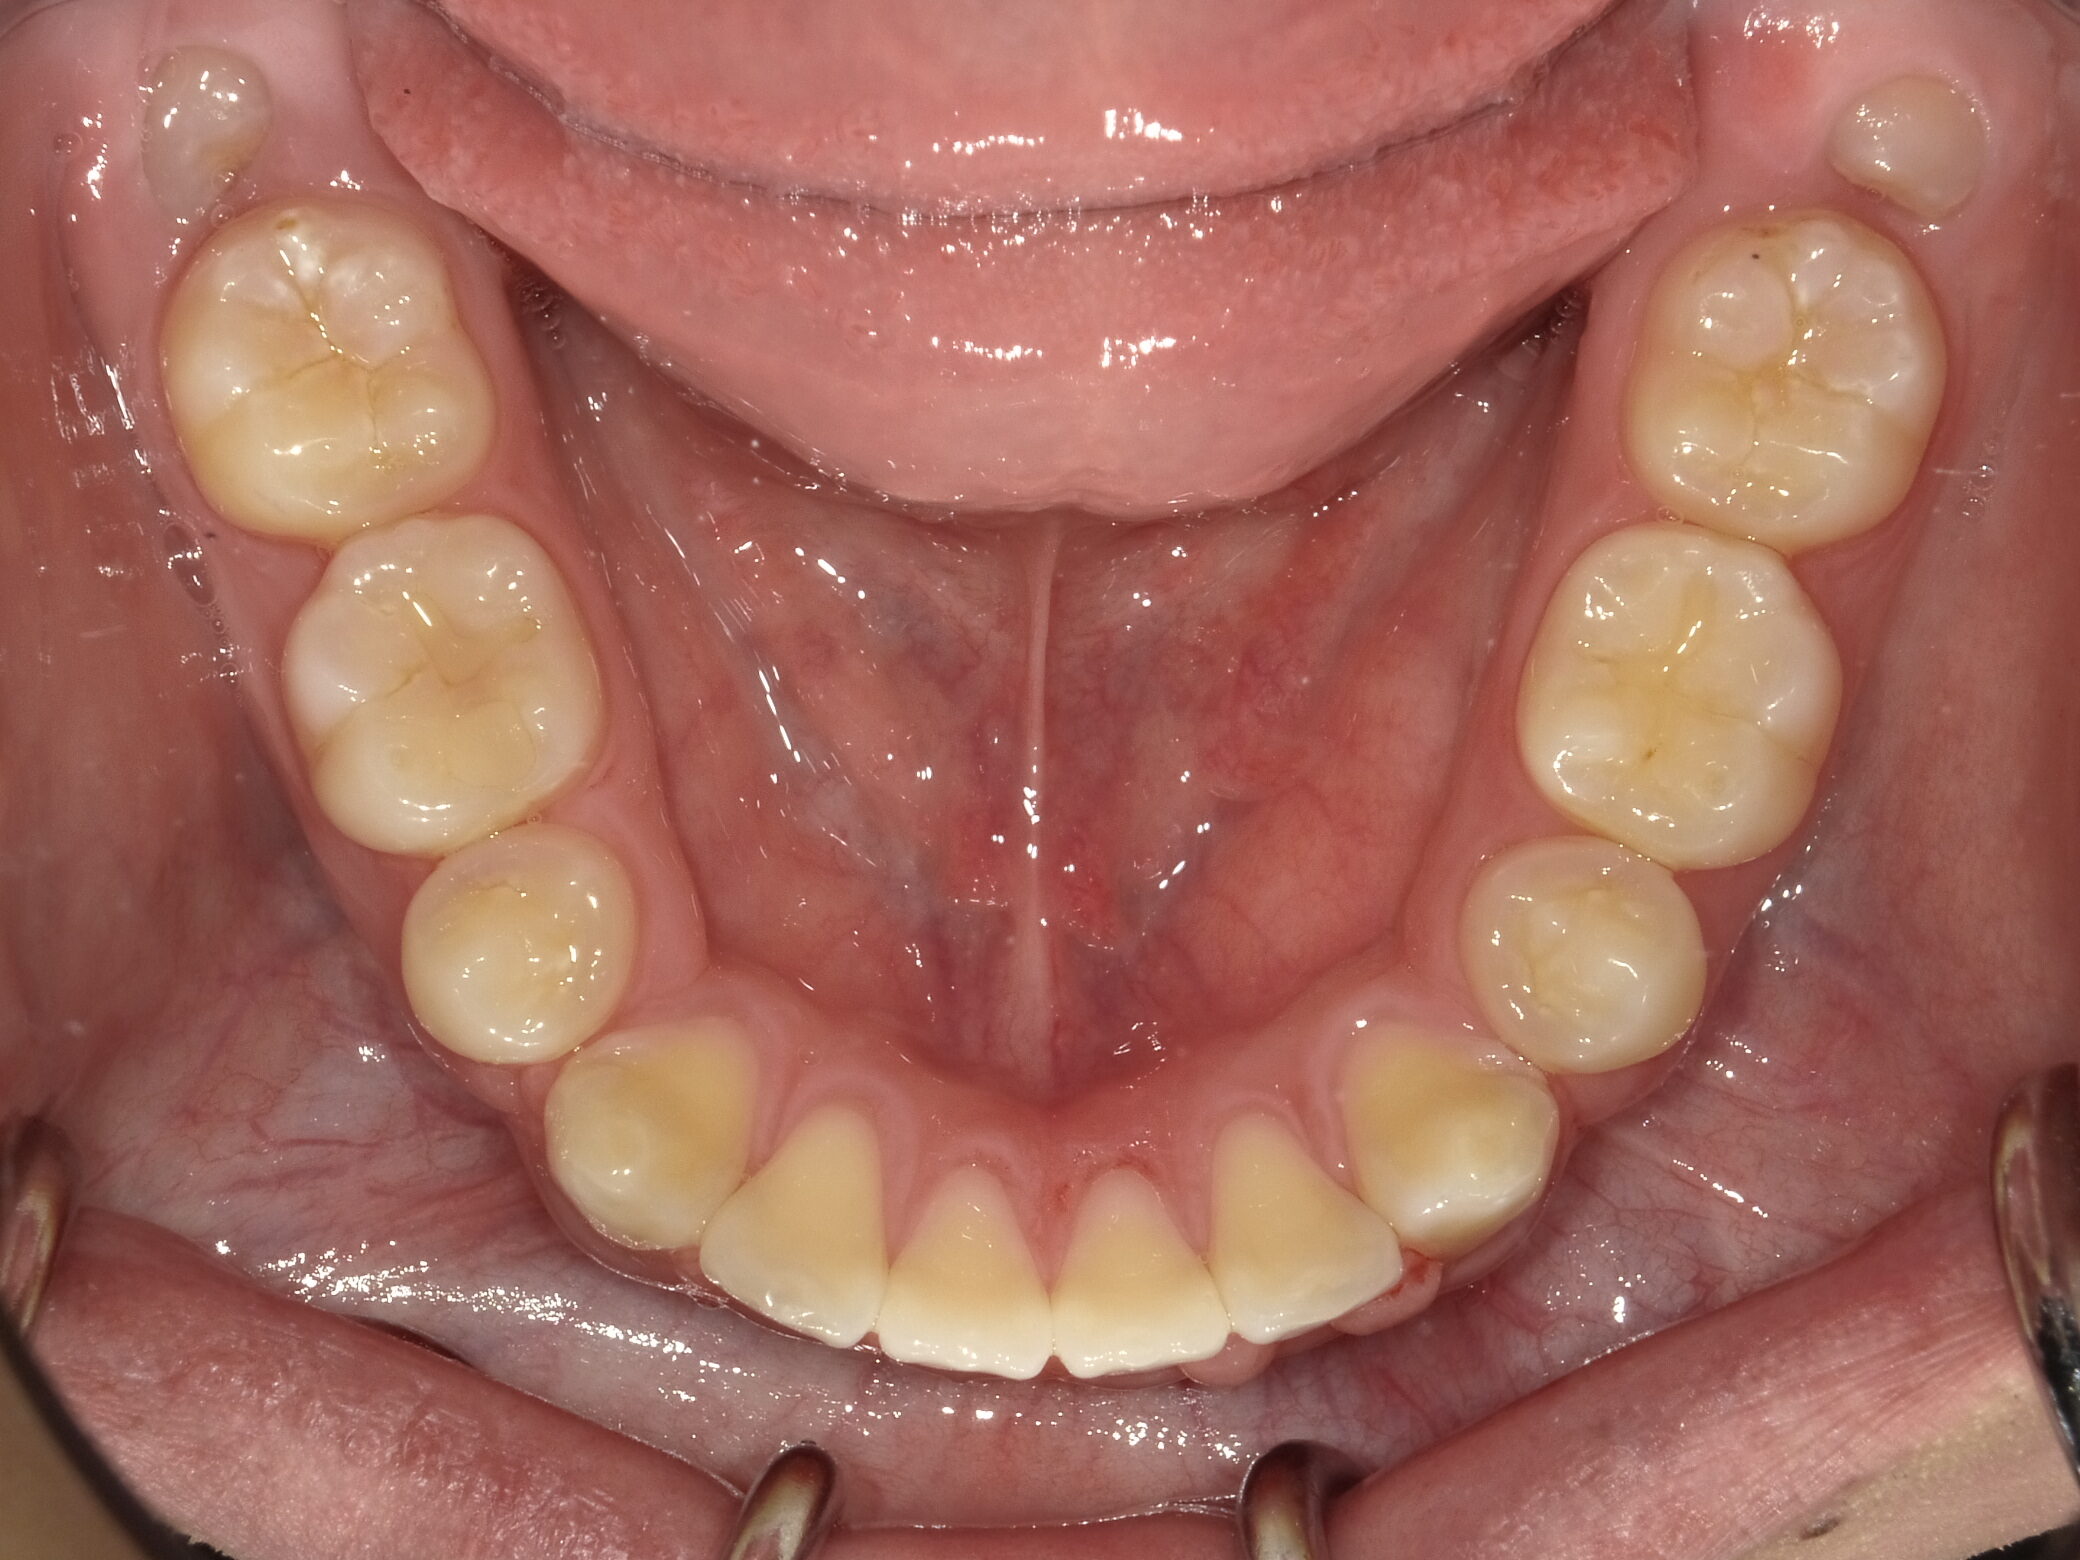

| 症例分類 | 上下顎前突 |

|---|---|

| 主訴 | 前歯が出ていて、口が閉じにくい |

| 年齢 | 20歳0ヶ月 |

| 性別 | 男性 |

| 抜歯部位 | 上下顎両側第一小臼歯 |

| 使用装置 | 歯の表側からのマルチブラケットによる矯正装置 |

| 治療期間 | 2年10ヶ月 |

| 保定装置 | 取り外し式保定装置 |

| 費用 | 相談料0円、検査料55,000円 動的矯正治療費935,000円 調整料6,600円×28回分 保定装置料0円 |

| リスク・注意点 | 上下の個々の歯の大きさに対して上下の顎が小さく歯が並ぶスペースが不足したために上下の前歯が前方に傾斜して、上下顎前突が生じています。これらを改善するために、上下顎両側第一小臼歯を抜歯して、このスペースを用いて歯を排列しました。歯の動き方には個人差があり、予想された治療期間が延長する可能性があります。 治療中は矯正歯科装置が歯の表面に付いており、歯が磨きにくくなるため、むし歯や歯周病が生じるリスクが高まります。ハミガキを適切に行ってお口の中を常に清潔に保ち、さらに、かかりつけ歯科医に定期的に受診することが大切です。 顎間ゴムの使用状況、定期的な通院など、矯正歯科治療には患者さんの協力が必要であり、それらが治療結果や治療期間に影響します。 治療の経過によっては当初予定していた治療計画を変更する可能性があります。 歯を動かすことにより歯根が吸収することがあります。 保定装置の装着時間が十分確保できない場合、歯並びや、咬み合せの「後戻り」が生じる可能性があります。 |